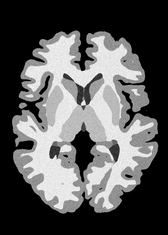

4.2 Registration to a 100 micron ex-vivo brain MRI volume

To showcase the efficacy of our method on real large scale images, we register a 250 in-vivo MRI image (Lüsebrink et al., 2017) to a 100 ex-vivo FLASH human brain volume (Edlow et al., 2019). This represents an inverse problem with more than 11.2B optimizable parameters (compared to 20M for clinical datasets), or 44.8GB of GPU memory. The entire problem does not fit on most GPUs, necessitating distributed multimodal registration. We optimize a composite transform - affine followed by a diffeomorphic mapping; details can be found in Section E.1. Multimodal deformable registration took 58 seconds on 8 NVIDIA A6000 GPUs, which is unprecedented at this resolution. Fig. 6 shows qualitative results, highlighting the ability to register highly detailed structures such as cerebellar white matter; these structures are not visible at macroscopic scales. The resultant advantages of performing registration at this scale can allow researchers to characterize the neuroanatomy at microscopic resolutions and allow morphometric analysis of cortical layers and subcortical nuclei among other structures.